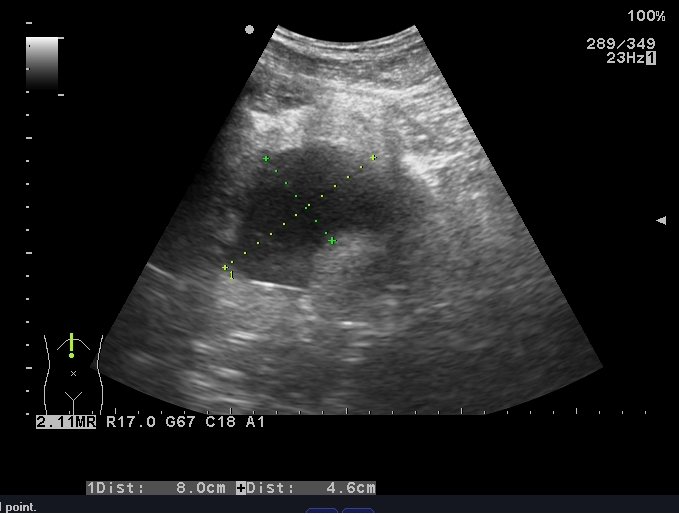

患者入院后完善相关检查,血常规:白细胞6.73×109/L,中性粒细胞4.87×109/L,血小板126×109/L;C-反应蛋白 > 90 mg/L;降钙素原7.6 ng/mL;凝血功能:PT 15 s。盆腔超声显示:骶前间隙可见一80 mm×46 mm的无回声区,内可见斑点样中强回声(图 2)。排除禁忌后,于入院当晚行超声引导下穿刺置管引流术,由于脓肿位置较深,经腹途径有肠管﹑膀胱和直肠的遮挡,所以本中心决定选择超声引导下经臀穿刺引流术。

|

| 图 2 盆腔超声显示:骶前间隙可见一80 mm×46 mm的无回声区,内可见斑点样中强回声 |